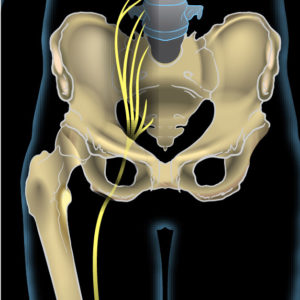

The sciatic nerve is the longest nerve in your body. It runs from the back of the pelvis and all the way down both legs, finishing at your feet. It can cause pain, numbness and a tingling sensation When the nerve is irritated or compressed. This then radiates from your lower back and travels down one of your legs to your foot and toes.